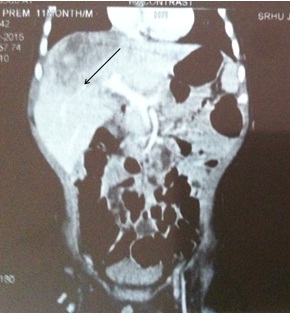

The patient was given 3 cycles of chemotherapy with intravenous injection Doxorubicin 5 mg in 50 ml Normal Saline (NS) over 6 hours for 3 days and injection Cisplatin 4mg in 50ml NS over 4 hours for 5 days. One unit of Fresh Frozen Plasma (FFP) was administered at the time of admission. Post chemotherapy CT scan showed a reduction in the size of liver mass [Table/Fig-4]. The child has tolerated chemotherapy well and is attending follow up clinics.

Post chemotherapy CT film showing regression of liver size.